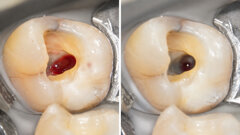

Bruxelles, Belgique : La Commission européenne a décidé d'examiner les risques de l'utilisation du mercure dans les amalgames dentaires. Comme certains États membres ont déjà restreint substantiellement l'utilisation des amalgames dentaires, la Commission veut étudier cette question en détail, en tenant compte de tous les aspects pertinents de son cycle de vie. L'étude doit être conclue en Juin 2012.

L'objectif de l'étude porte plus sur l'environnement plutôt que sur les aspects médicaux de l'amalgame dentaire. Alors que le débat scientifique sur les effets potentiels sur la santé de l'utilisation des amalgames dentaires est encore une controverse, la nécessité d'une bonne gestion des déchets d'amalgames dentaires n'est pas contestée. Il est prévu que d'une quantité importante de mercure provenant des amalgames dentaires, estimée à plus de 1.000 tonnes pour toute la population de l'UE, va sans doute se retrouver finalement dans l'environnement, par exemple par libération dans le sol par l'intermédiaire d'inhumations, ou même par l'émission directe dans l'atmosphère après crémations, sauf si des mesures pertinentes sont envisagées.

Dental Tribune Online a appris que la Commission a récemment attribué un contrat à un consultant pour étudier la situation actuelle par rapport à la quantité de mercure utilisée dans les amalgames dentaires dans l'UE et pour identifier les mesures qui pourraient réduire son impact environnemental. Les conclusions de l'étude seront présentées et discutées lors d'un atelier à Bruxelles, en mars 2012, et les intervenants potentiels auront l'occasion de soumettre leurs commentaires et suggestions. Selon la Commission européenne, les parties intéressées sont invitées à apporter une contribution au cours du processus et à exprimer leur intérêt pour participer à l'atelier.

La Commission prendra les résultats de l'étude en compte, ainsi que les développements internationaux pertinents, avant de procéder à de potentielles mesures politiques.